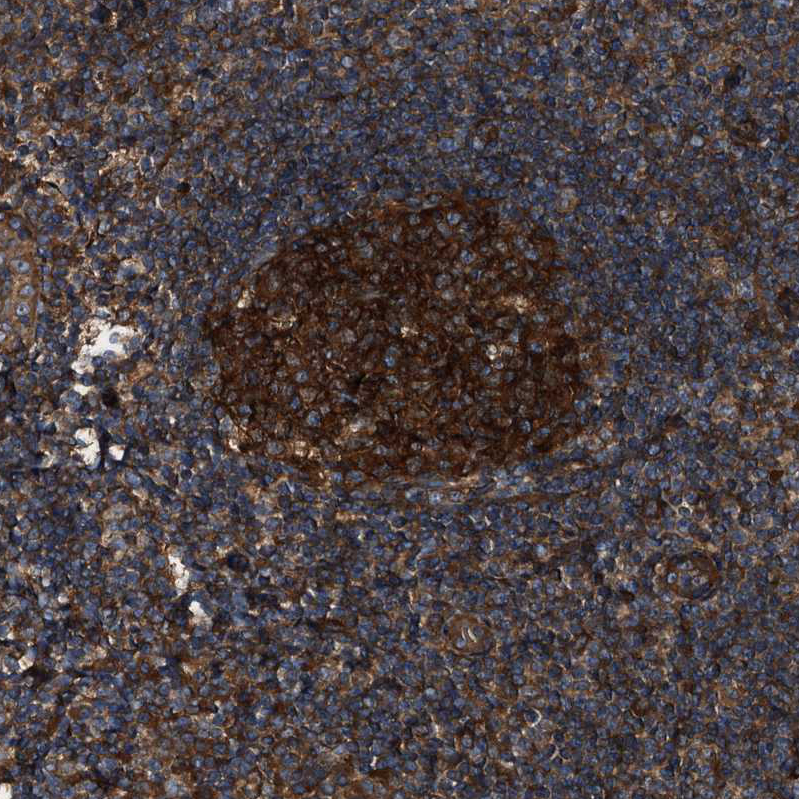

Immunohistochemical staining of human cerebral cortex, colon, lymph node and testis using Anti-PEX5 antibody HPA039259 (A) shows similar protein distribution across tissues to independent antibody HPA039260 (B).